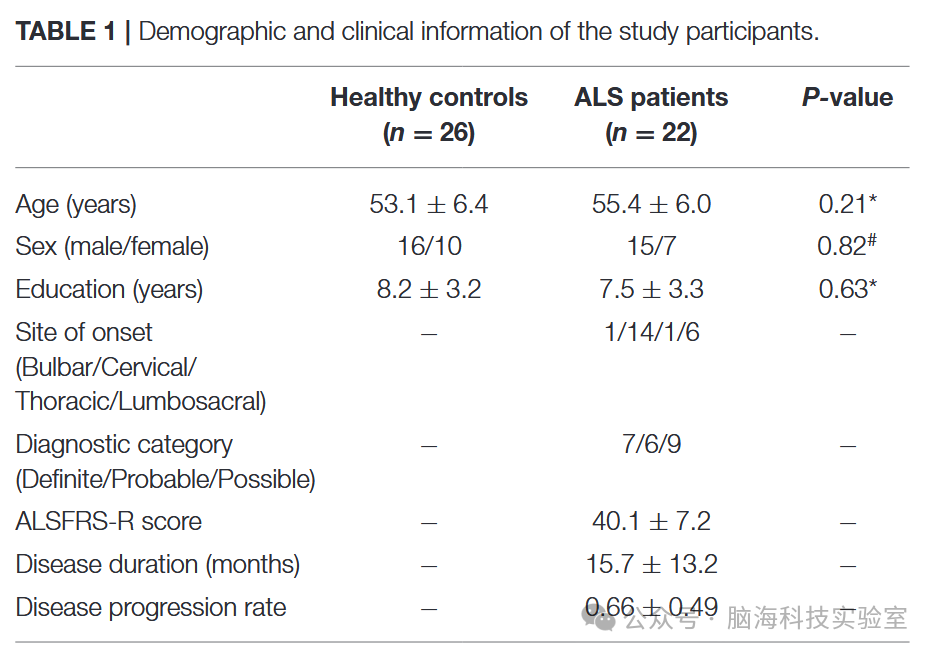

2. 被试

本研究共纳入22名ALS患者(1例为家族性,21例为散发性)以及26名健康对照者(HC)。采用El Escorial标准对ALS进行诊断,同时使用修订版ALS功能评分量表(ALSFRS-R)评估疾病的严重程度。研究参与者的临床和人口学信息见表1。患者组和对照组在年龄、性别或教育水平方面均未观察到显著差异(详细信息见表1)。

表1